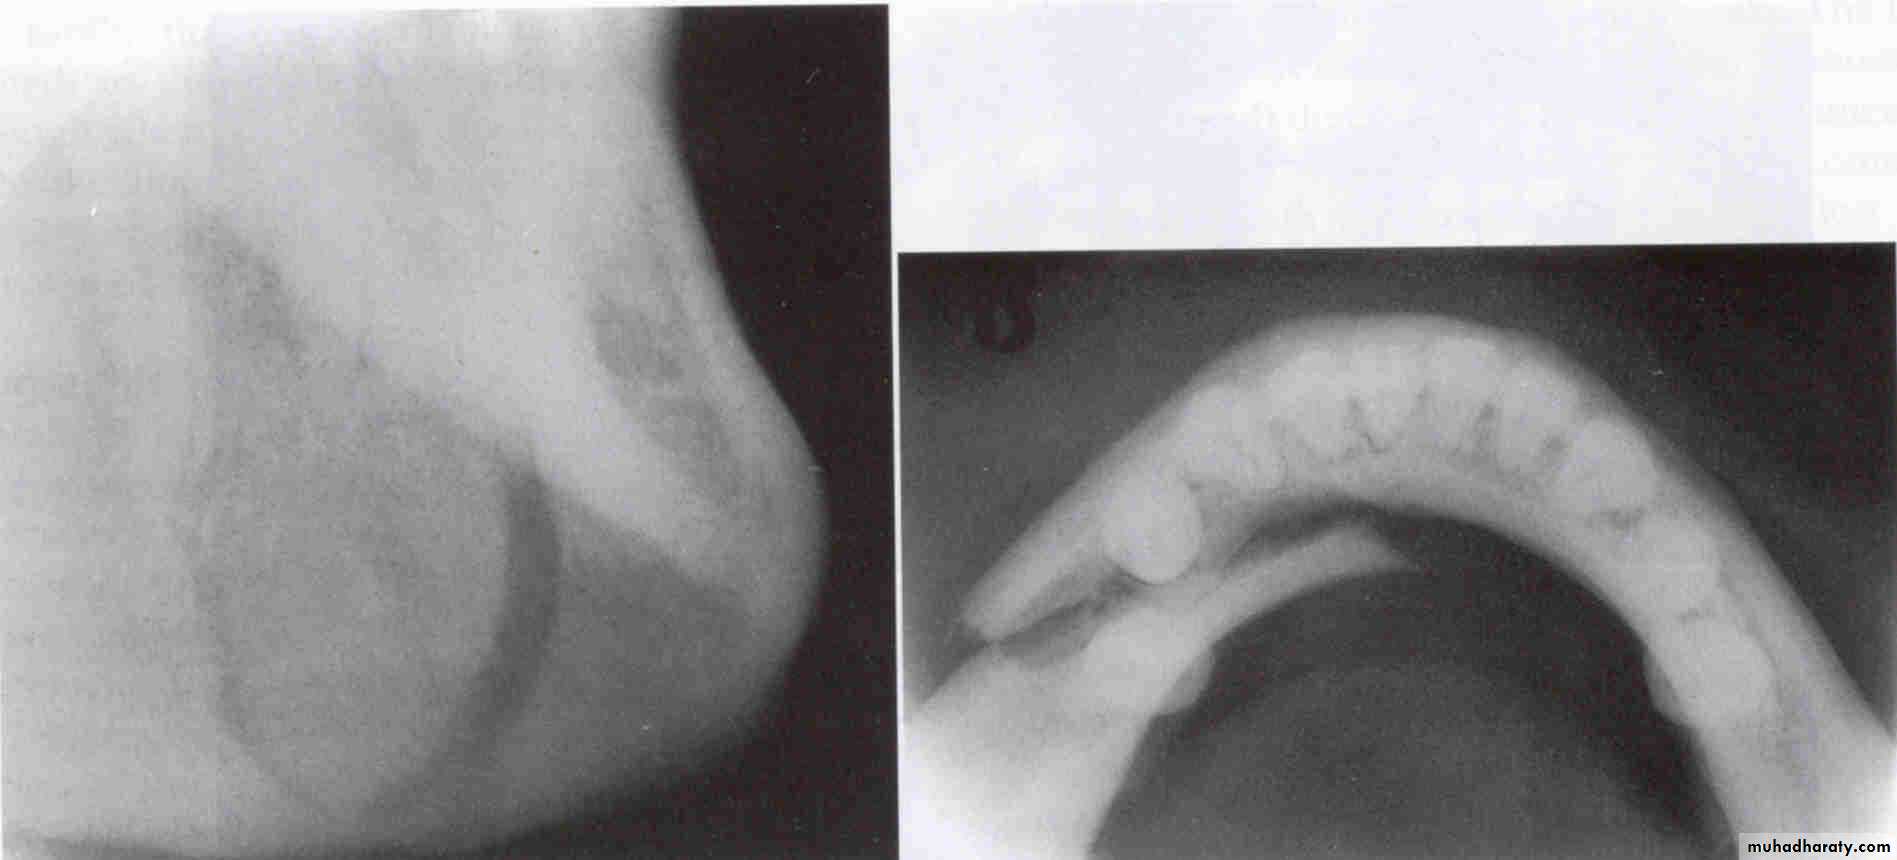

Occlusal viewA PA. film identify the location of an object vertically and in a horizontal (mesiodistal) direction, since it is a 2D. Therefore we need another method for locating objects in a buccolingual direction. The two primary methods of determining the buccolingual location of objects are:

Right-Angle Technique (Miller’s Technique) (Occlusal projection)

Primarily identifies buccolingual location, but mayalso confirm mesiodistal location seen on periapical

Miller’s TechniqueUsually Indicated for Mandibular Third molar area.

Two radiographs made are positioned at right angles to each other.

LOCALIZES in 3 Dimensions

DISADVANTAGESCan be used in mandible but not that useful in maxilla due to superimpositions.